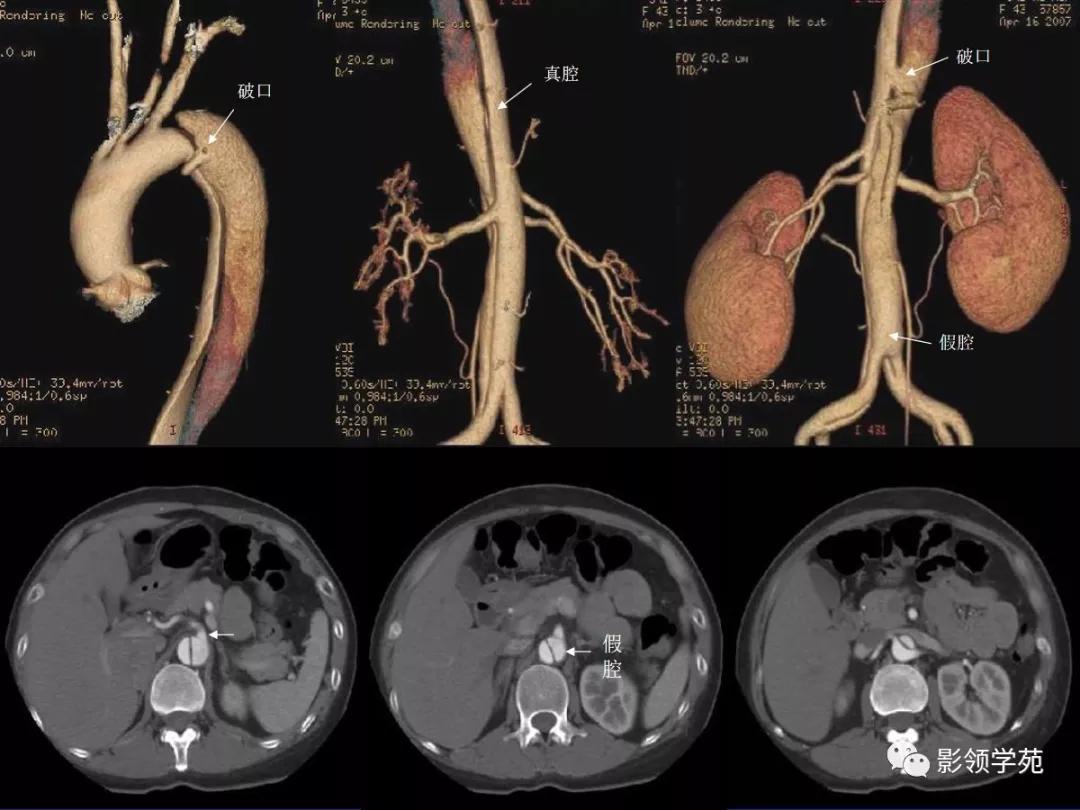

- 主动脉夹层(aortic dissection, AD)

- 真假“双腔” ,存在交通

- 远段同时存在再破口